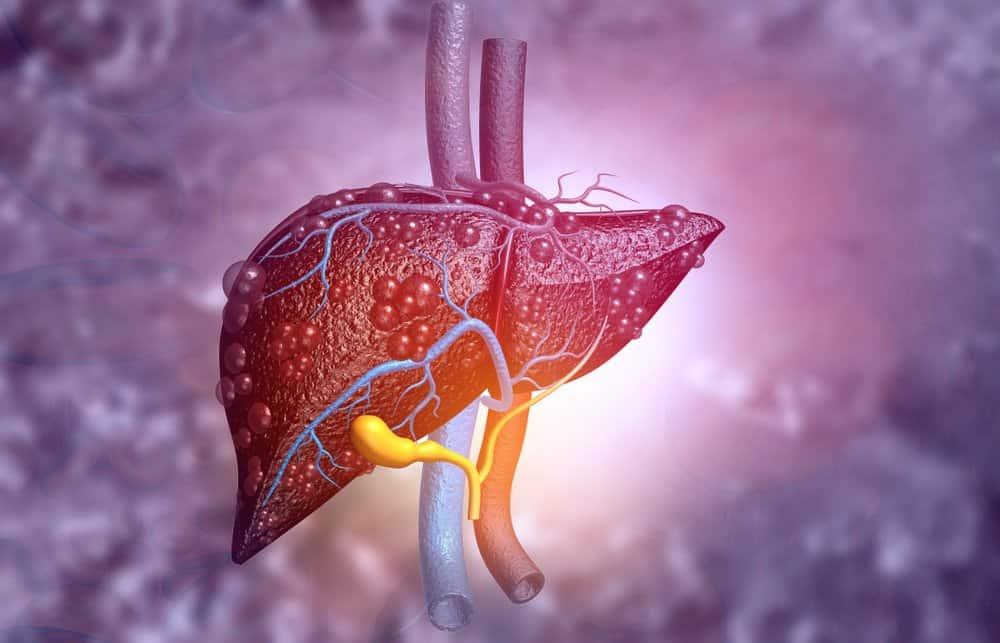

1. Xơ gan là bệnh gì?

Xơ gan là tiến trình mô gan bình thường bị thay thế lan tỏa bởi mô sợi và những nốt tân sinh, không hồi phục được.